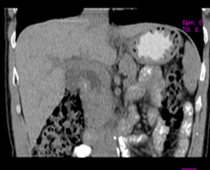

患者,男,57,常年不吃午饭,近一个月来腹部隐痛,无明显黄疸,明天进行增强扫描,图象另上传,麻烦各位帮忙一起看看讨论讨论

肝外胆管扩张,胰头增大,肠系膜上静脉似有包埋征象。

考虑:胰头占位性病变,建议增强进一步检查。

肝外胆管扩张,胰头增大,占位性病变可能性大.

肝外胆管稍扩张,胰腺钩突略增大,但外形尚可,境界清楚。(常年不吃午饭)提示胰腺炎可能大,肿瘤第二步考虑。

支持考胰头占位性病变,感觉十二指肠壁不规则增厚,不排除十二指肠降部占位可炎症

胰头增大,考虑胰头占位性病变。

胰头增大,胆总管增宽,考虑胰头癌可能性大,明天看增强片有助诊断.